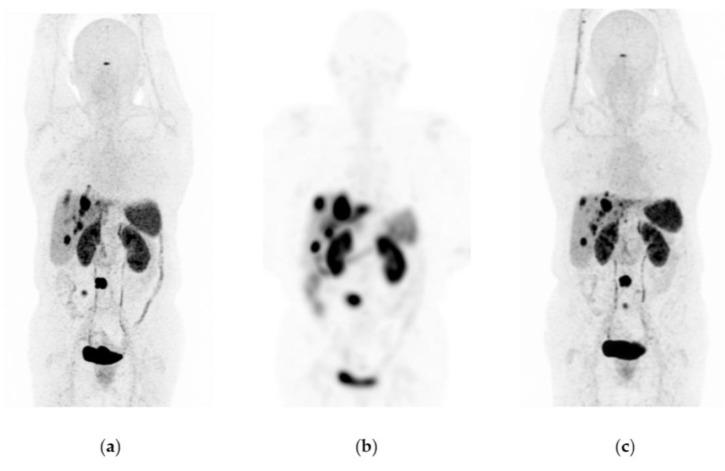

Lu-iPSMA is a novel radioligand developed at ININ-Mexico with a high affinity for the PSMA protein heavily expressed in cancer cells of approximately 95% of patients with metastatic castration-resistant prostate cancer (mCRPC). Lu-DOTATOC is a patent-free radioligand, molecularly recognized by somatostatin receptors (SSTR-2) overexpressed in cancer cells of about 80% of patients with metastatic gastroenteropancreatic neuroendocrine tumors (GEP-NET). This translational research aimed to determine the efficacy and safety of Lu-iPSMA and Lu-DOTATOC developed as GMP pharmaceutical formulations for treating progressive and advanced mCRPC and NET. One hundred and forty-five patients with mCRPC and one hundred and eighty-seven subjects with progressive NET (83% GEP-NET and 17% other NET), treated with Lu-iPSMA and Lu-DOTATOC, respectively, were evaluated. Patients received a mean dose of 7.4 GBq per administration of Lu-iPSMA (range 1-5 administrations; 394 treatment doses) or Lu-DOTATOC (range 2-8 administrations; 511 treatment doses) at intervals of 1.5-2.5 months. Efficacy was assessed by SPECT/CT or PET/CT. Results were stratified by primary tumor origin and number of doses administered. Patients with mCRPC showed overall survival (OS) of 21.7 months with decreased radiotracer tumor uptake (SUV) and PSA level in 80% and 73% of patients, respectively. In addition, a significant reduction in pain (numerical scale from 10-7 to 3-1) was observed in 88% of patients with bone metastases between one and two weeks after the second injection. In the GEP-NET population, the median progression-free survival was 34.7 months, with an OS of >44.2 months. The treatments were well tolerated. Only ten patients experienced grade ≥ 3 myelosuppression (3% of all patients). The observed safety profiles and favorable therapeutic responses demonstrated the potential of Lu-iPSMA and Lu-DOTATOC to improve overall survival and quality of life in patients with progressive and advanced mCRPC and NET.

镥-PSMA是墨西哥国立核科学研究所研发的一种新型放射性配体,对约95%的转移性去势抵抗性前列腺癌(mCRPC)患者癌细胞中高表达的PSMA蛋白具有高亲和力。镥-奥曲肽是一种无专利的放射性配体,可被约80%的转移性胃肠胰神经内分泌肿瘤(GEP-NET)患者癌细胞中过表达的生长抑素受体(SSTR-2)分子识别。这项转化研究旨在确定作为药品生产质量管理规范(GMP)制剂开发的镥-PSMA和镥-奥曲肽治疗进展期和晚期mCRPC及神经内分泌肿瘤(NET)的疗效和安全性。分别对145例mCRPC患者和187例进展期NET患者(83%为GEP-NET,17%为其他NET)进行了评估,这些患者分别接受了镥-PSMA和镥-奥曲肽治疗。患者接受镥-PSMA(范围为1至5次给药;394个治疗剂量)或镥-奥曲肽(范围为2至8次给药;511个治疗剂量),每次给药平均剂量为7.4GBq,给药间隔为1.5至2.5个月。通过单光子发射计算机断层扫描/计算机断层扫描(SPECT/CT)或正电子发射断层扫描/计算机断层扫描(PET/CT)评估疗效。结果按原发肿瘤来源和给药剂量数进行分层。mCRPC患者的总生存期(OS)为21.7个月,分别有80%和73%的患者放射性示踪剂肿瘤摄取(SUV)和前列腺特异抗原(PSA)水平降低。此外,在第二次注射后1至2周内,88%的骨转移患者疼痛显著减轻(数字评分从10 - 7降至3 - 1)。在GEP-NET人群中,无进展生存期的中位数为34.7个月,总生存期>44.2个月。这些治疗耐受性良好。只有10例患者出现≥3级骨髓抑制(占所有患者的3%)。观察到的安全性概况和良好的治疗反应表明,镥-PSMA和镥-奥曲肽有潜力改善进展期和晚期mCRPC及NET患者的总生存期和生活质量。